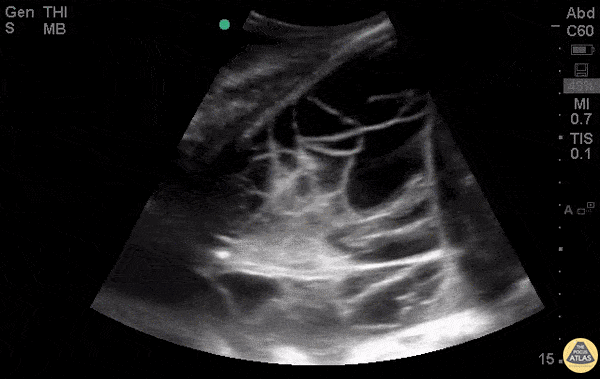

WCUME 2017 Submission for "Best POCUS" 26 y/o M with Hodgkin Lymphoma with a very complicated, septated, fluid-filled PLAPS - posterolateral alveolar or pleural syndrome. Aspiration of the fluid was exudative. Dr. Yasmin Sadri Savadjani - Firoozgar General Hospital